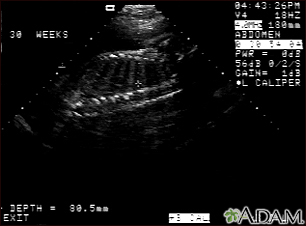

Ultrasound, normal fetus - spine and ribs

This is a normal fetal ultrasound performed at 30 weeks gestation. In the middle of the screen, a clear outline of the spine and ribs is visible. The cross hair is between two ribs just above the spine.